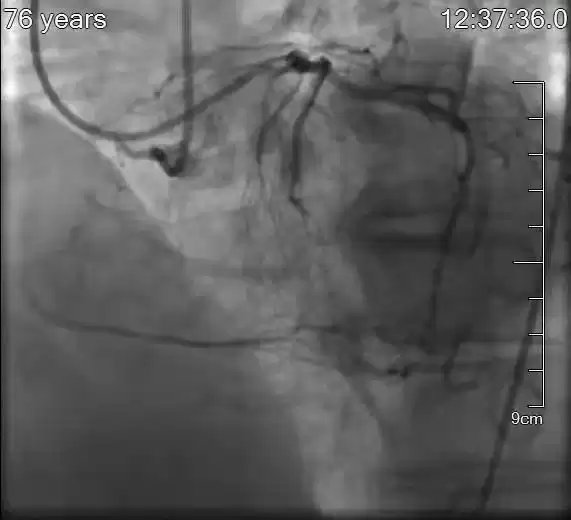

患者为76岁老年男性,半年前曾因急性心肌梗死接受治疗,但右冠脉(RCA)仍为慢性完全闭塞。此次因胸闷再发入院,心脏功能较差,射血分数仅40%。影像显示,RCA近端迂曲闭塞,侧枝循环扭曲,手术难度与风险极高。

术前影像:揭示复杂病变